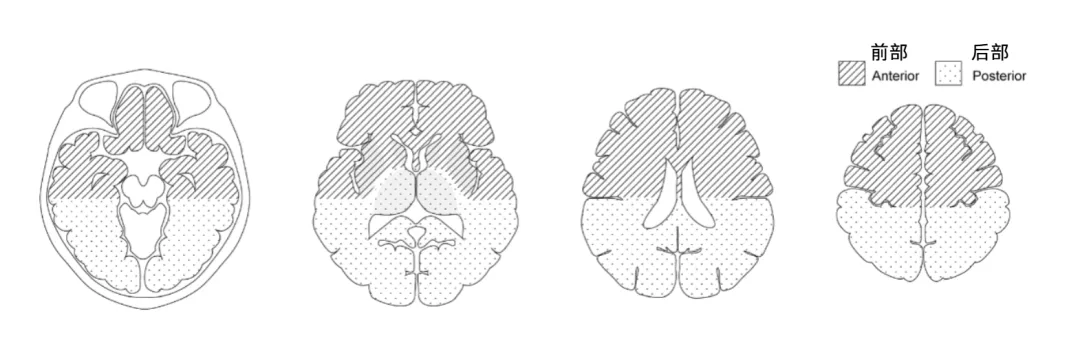

这项研究共纳入80例成人出血型烟雾病患者,依据第一次CT显示的出血部位,划分为两大类型。

前部出血:位于基底节、额叶、侧脑室前部等区域,根源在于大脑前动脉或中动脉穿支血管的破裂。后部出血:位于丘脑、枕叶、侧脑室后部等区域,主要源于大脑后动脉或脉络膜动脉异常分支的破裂。

后部出血的代表性 CT 图像

A:顶叶及枕叶出血 | B:原发性脑室内出血(后部分布型)C:侧脑室后部室管膜下区出血(箭头所示)

A:丘脑出血 | B:颞叶后半部出血 | C:胼胝体后半部出血

前部出血的代表性 CT 图像

A:壳核出血 B:尾状核头出血 C:额叶出血 D:颞叶前半部分出血

A:侧脑室前部室管膜下区出血;B:脑池前半段蛛网膜下腔出血;C:起源不明、弥漫分布的原发性脑室内出血